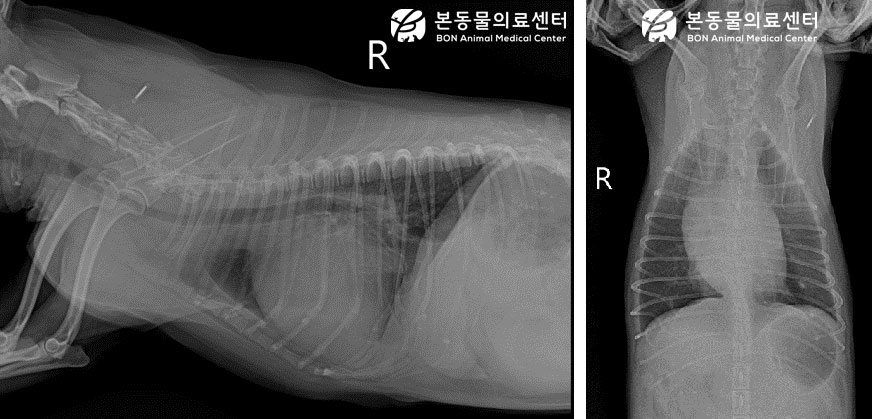

흉부 방사선 및 심장 초음파 검사 상 이첨판의 퇴행성 변화 및 양심 (좌심, 우심) 종대 및, 복부 초음파 검사 상 간울혈 및 소량의 복수도 보였습니다. 추가적으로 심장 초음파 검사 시 스캔이 어려울 정도로 부정맥이 심하게 확인되었는데, 추가적인 심전도 검사 시 심방 세동으로 진단되었습니다.

영상검사(흉부방사선) – 흉부방사선 결과 심한 심장 종대 보임.